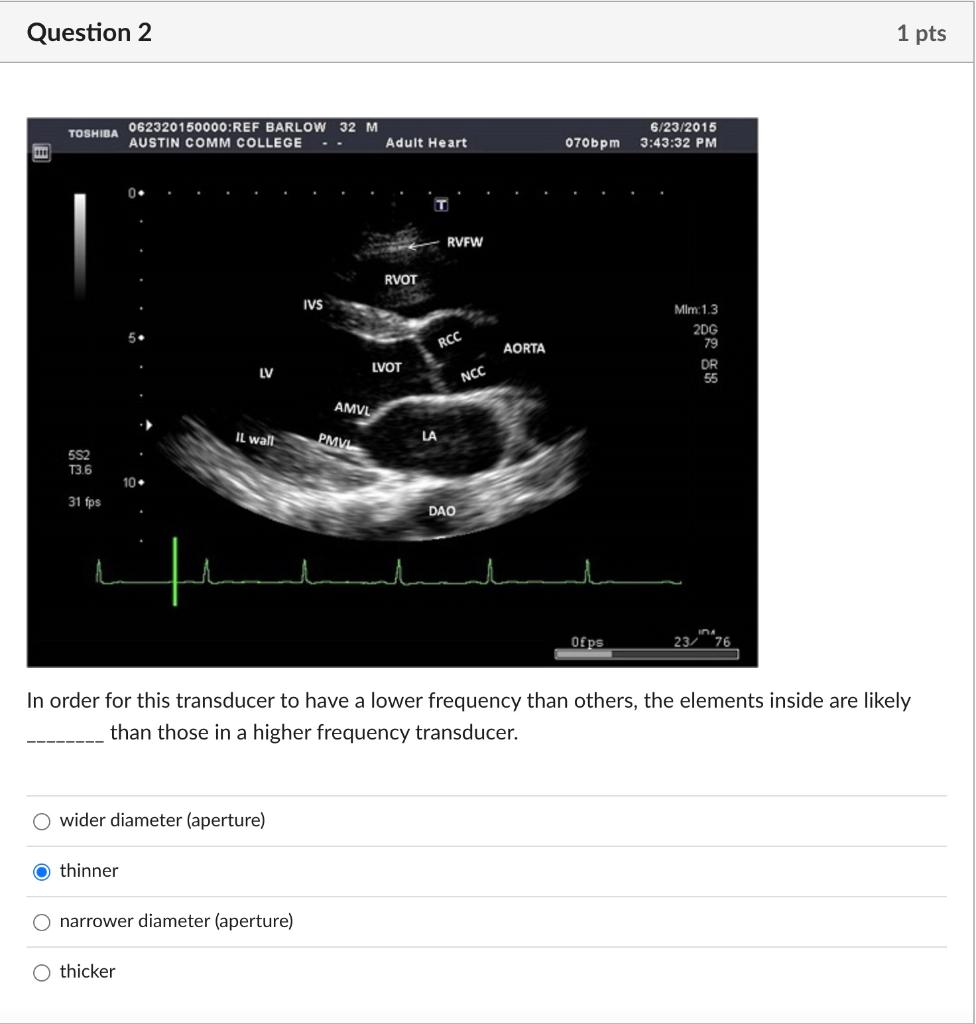

Solved In order for this transducer to have a lower Lowering The Transducer Frequency Will Transducers can be set to receive the incident frequency and the harmonic frequencies, combining them to create a higher resolution image. Diameter or frequency is changed so that the ratio becomes 10, the total beam angle will be reduced to approximately 6°. The bandwidth of a transducer defines its frequency output, which, in turn, affects its performance. A) decrease the. Lowering The Transducer Frequency Will.